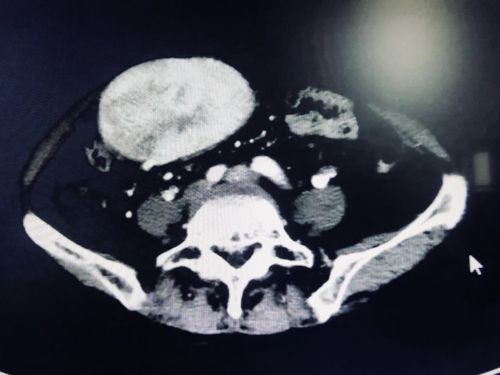

肿瘤巨大,长到了盆腔内。

9月20日,陈梅福、成伟、朱朝庚、刘昌军、李国光等医护人员在吴金术教授的指导下轮番上阵,历时10小时,为李群英成功切除一个约30×40×10cm3大小、重达3.3公斤的腹膜后脂肪肉瘤,被肿瘤累及的胰腺、脾脏、95%的胃、胆囊、胆总管下段、十二指肠、空肠上段、横结肠等8个脏器也被一同切除,仅切下的肠子就有六七十厘米长,并为她重建消化道。